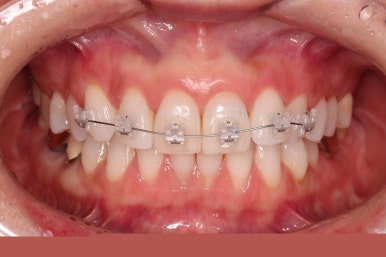

윗니에만 장치를 부착하고 부분교정을 시작했습니다.

환자분이 연산동부분교정 선택하신 장치는 엠파워 클리어라고 하는 자가결찰 세라믹 장치입니다.

장치 부착한 모습 참고해 주시고요.